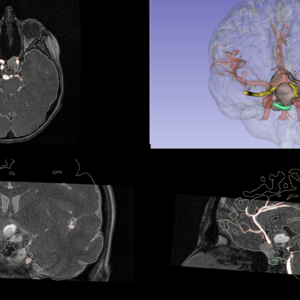

We are pleased to announce that at the 35th Congress of the European Society for Pediatric Urology, held in Vienna from September 3-6, 2025 (https://jointmeeting2025.espu.org), the collaboration between Printmed and the Pediatric Surgery Department of the Vittore Buzzi Children’s Hospital (directed by Professor Gloria Pelizzo) has led to new international recognition, with First Prize in the Video Abstract category for the paper entitled:

ADVANCING NEUROBLASTOMA SURGERY THROUGH VIRTUAL REALITY

(VR) AND INDOCYANINE GREEN (ICG) FLUORESCENCE IMAGING“.

This international recognition demonstrates how, thanks to the ongoing collaboration between Printmed and its clinical counterpart, the use of new surgical technologies such as Virtual Reality can lead to extremely interesting results and clinical applications.